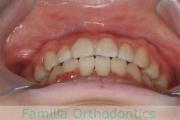

No.22V-409

- 叢生

- 16歳

- 女性

- 44

- 8|58

- FEA

- 86万円

八重歯を治したいということで来院されました。下あごの左ずれのある上顎前突(出っ歯)・叢生(でこぼこ)でしたので、上は左右から、下はで左のみ小臼歯を抜歯して、歯科矯正用アンカースクリューとマルチブラケット法にて治療を行いました。2年強、30回程度の通院が必要でした。

上下とも前歯の叢生(でこぼこ、凹凸、ガタガタ)があるため、保定を怠ると後戻りのリスクがあります。